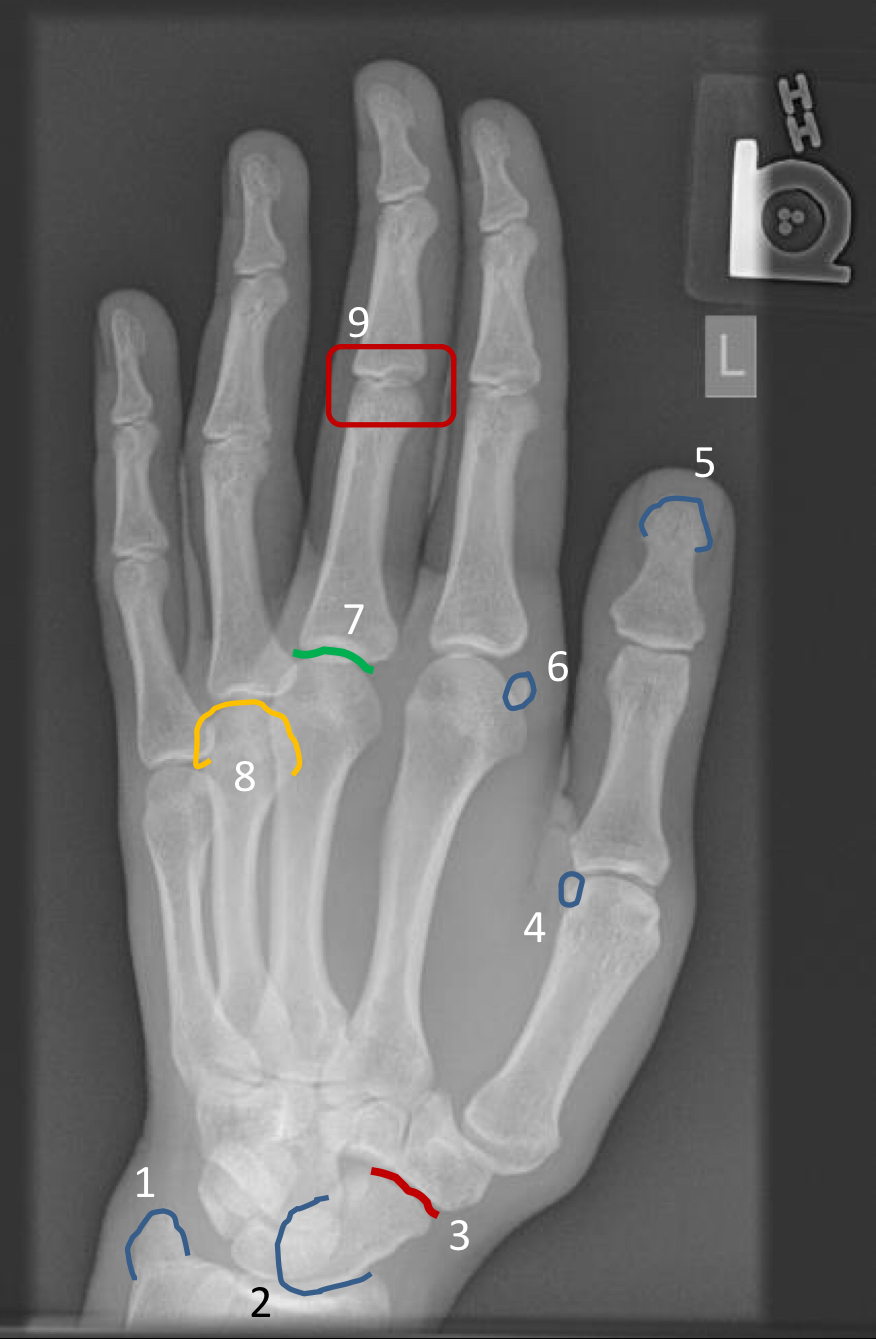

1?

scaphoid tubercle

2?

hook of hamate

3?

hypothenar eminence

4?

1st interphalangeal joint (poorly visualized)

5?

2nd metacarpal diaphysis

6?

“condylar” appearance at the head of metacarpal